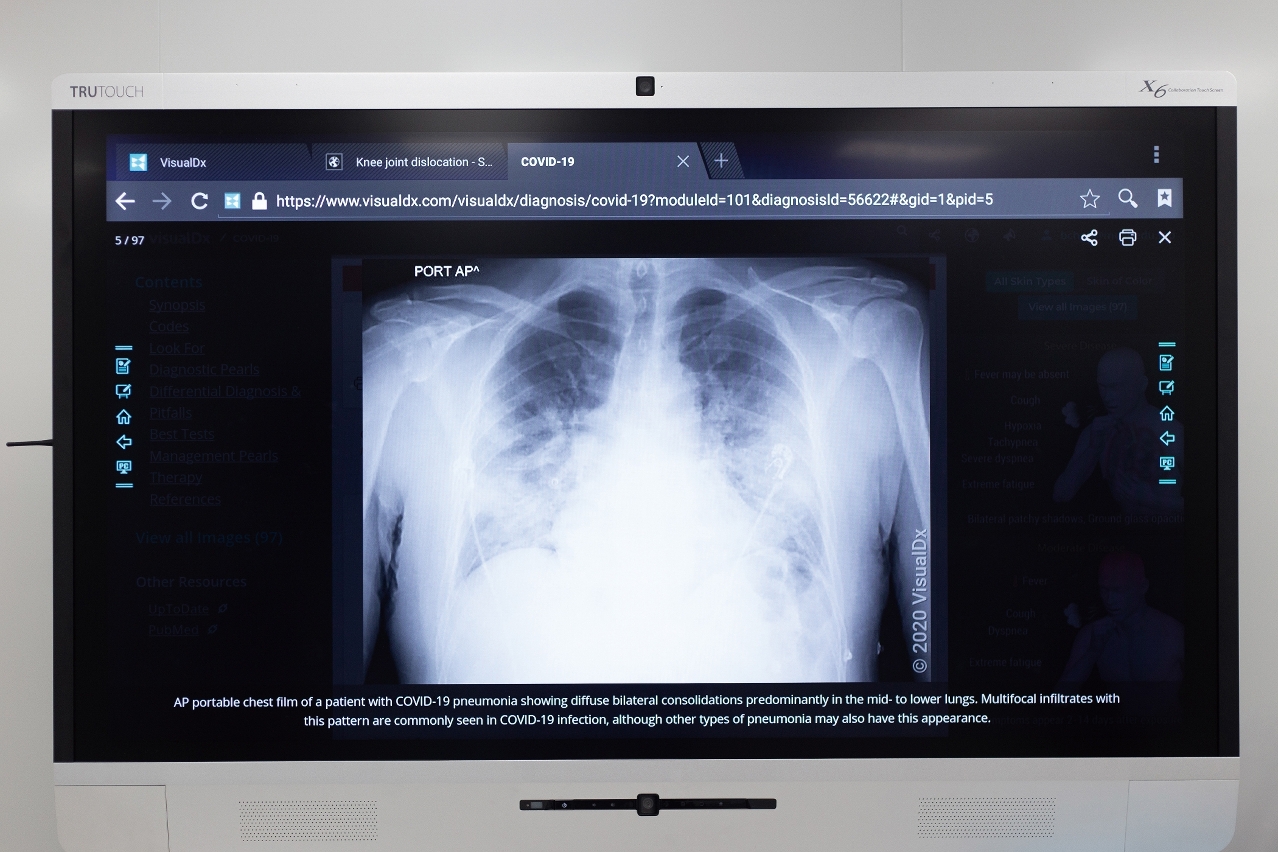

張康教授介紹,運用深度學習(Deep Learning)、遷移學習(Transfer Learning)、語義分割(Semantic Segmentation)等多種人工智能前沿技術,開發出基於胸部CT(Computed Tomography,電腦斷層攝影)和X-ray(俗稱「X光」)的新冠肺炎人工智能系統,可以對胸部醫學影像進行快速輔助診斷。他說:「深度學習是近十年來,在人工智能領域發生的顛覆性技術,這技術以電腦作為媒介,模擬出人類大腦一樣的記憶及思維。在此基礎上,我們只要整合所有大數據及人工智能深度學習的演算法,通過訓練就能夠得到一個非常準確的新冠肺炎診斷工具。」

使用人工智能診斷技術,可以在病患的數百張胸部醫學影像中快速準確地找出病灶。

AI診斷技術的出現,有效減輕醫療人力資源及物資的消耗,促進疫情診斷方向的全球化交流,對新冠肺炎的研究起到關鍵性作用。張康教授指出,每名病患都會拍攝數百張胸部醫學影像,其中顯示出病灶的便可能有數十張。「即使資歷較深的醫生,亦要約20分鐘,才能通過胸部醫學影像判斷出患者是否感染了新冠病毒及肺部病灶所在,較為耗時。若使用AI診斷技術,則僅需20秒就可以完成輔助診斷。」AI診斷技術除有快速判斷功能外,還可以對胸部醫學影像的病灶進行自動識別、標註及定量分析,準確率達到90%以上,並可預測病灶的發展情況,有利醫生及時診治,亦有助醫務人員進行藥物效果評估,實現對新冠肺炎病患的全生命週期管理。